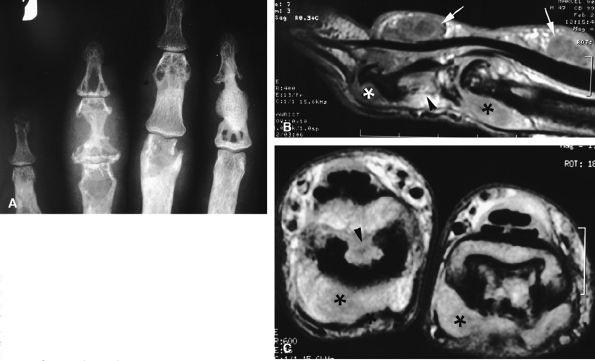

FIGURE 11.31 ● Mallet finger. (A) Fracture avulsion (arrow) of the base of the distal phalanx (lateral view). (B) Sagittal T1-weighted images in a different case showing a tear of the terminal band of the extensor apparatus (arrows) with thickening of soft tissues. There is bone edema (arrowhead) of the base of the distal phalanx without fracture.

|